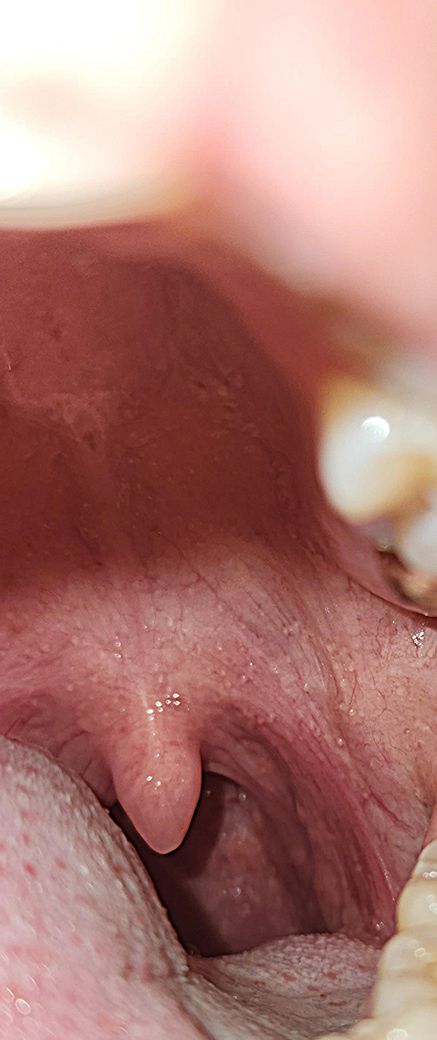

목이빨갛고부었다고했는데 수족구병변보이시나요?

목이빨갛게부어있다하셨어요.

오전에는 수포안보인다고하셨어요.

이정도 붓기와빨간정도면 열이날수도있을정도인가요?

• 1번 째 사진

사진을 보면 목이 많이 붉고 부어있는 것이 보입니다. 이 정도의 염증은 열을 동반할 수 있으며, 이는 신체가 감염과 싸우기 위해 반응하는 정상적인 과정입니다. 아이들의 수족구병이 있다면, 어른도 전염될 가능성이 있으므로 주의가 필요합니다. 수족구병의 경우 초기에는 인후염, 발열, 피로 등의 증상이 나타날 수 있으며, 이후 손, 발, 입안에 작은 물집이 생기기도 합니다. 오전에 의사께서 수포가 보이지 않는다고 하셨지만, 수족구병의 초기 단계일 수도 있습니다.